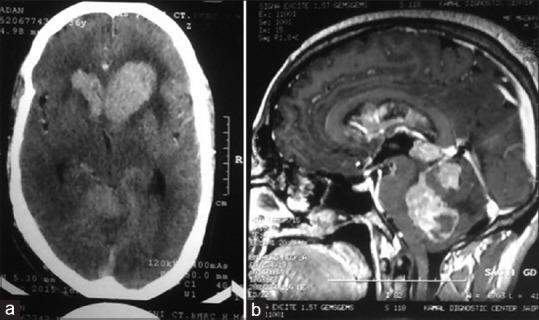

Primary central nervous system lymphoma (PCNSL) is a rare tumor that accounts for <1%-4% of primary CNS tumor. PCNSLs are class of non-Hodgkin's lymphomas which are primarily of diffuse large B-cell origin (90%), with remaining being T-cell lymphoma (10%). Author report a rare case of PCNSL presenting as an intracranial mass involving the entire ventricular system, in an immunocompetent 36-year-old male with severe headache, decreased vision, and unsteady gait. The diagnosis was obtained by histopathological and subsequent immunohistochemistry.

原发性中枢神经系统淋巴瘤(PCNSL)是一种罕见肿瘤,占原发性中枢神经系统肿瘤的不到1%-4%。PCNSL是非霍奇金淋巴瘤的一种,主要起源于弥漫性大B细胞(90%),其余为T细胞淋巴瘤(10%)。作者报告了一例罕见的PCNSL病例,表现为颅内肿块累及整个脑室系统,患者为一名36岁免疫功能正常男性,有严重头痛、视力下降和步态不稳症状。通过组织病理学及后续免疫组化检查得以确诊。